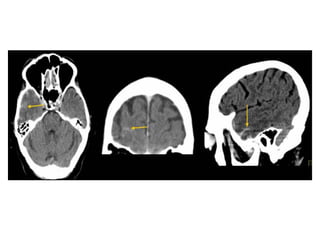

CT without contrast : Cord Sign , in the SSS (dotted arrow)

and the RTS (arrows)

Attenuated vein sign in both ICVs (thin arrows), in the SS (crossed arrow)

Hemorrhagic infarction in the temporal lobe (red arrow) , notice the dense

transverse sinus due to thrombosis (blue arrows)

CT without contrast , cerebral venous thrombosis